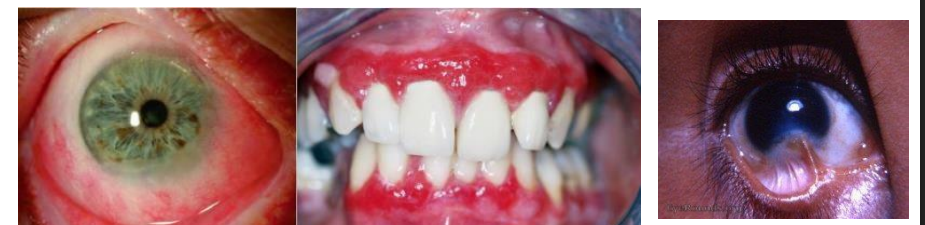

MFD EXAMS /23 6 1234567891011121314151617181920212223 You have 30 min to complete this exam. The timer will start once you begin Attention: Only a few minutes left! Please submit your answers soon. MFD 1 Get a quick sneak peek before the real exam !This trial quiz is designed to show you the question style, difficulty level, and how the options will appear on the platform. 1 / 23 1. What is the lethal dose and toxic dose of fluoride, management? Check 2 / 23 2. What the advantage of silver diamine over other methods and disadvantages ? Check 3 / 23 3. Method of topical fluoride application with concentration ? Check 4 / 23 4. What will happen if left untreated? Check 5 / 23 5. What changes that will happen if the habit stopped? Check 6 / 23 6. Give 3 of your initial stage of treatment? Check 7 / 23 7. What are the causes? Check 8 / 23 8. What is this? Check 9 / 23 9. Then they specified the type of pain and asked about the diagnosis Check 10 / 23 10. What other tests to check vitality of the pulp? Check 11 / 23 11. What are the factors will govern the Rx of Posterior cross bite ? Check 12 / 23 12. What are the factors that govern the treatment of anterior cross bite? Check 13 / 23 13. Name the appliance that you can use to treat this case? Check 14 / 23 14. Name 3 causes? Check 15 / 23 15. Name the most important clinical diagnostic information you need to know. (check RCSI intensive course )? Check 16 / 23 16. What do you see? Check 17 / 23 17. What is your treatment? Check 18 / 23 18. Name the investigations needed? Check 19 / 23 19. causes for gingival enlargement ? Check 20 / 23 20. What is the common side effect of this drug? Check 21 / 23 21. Name the drug that he may take to treat this condition? Check 22 / 23 22. The patient may have what? Check 23 / 23 23. What is this clinical condition? Check /31 2 12345678910111213141516171819202122232425262728293031 You have 30 min to complete this exam. The timer will start once you begin Attention: Only a few minutes left! Please submit your answers soon. MFD 2 Get a quick sneak peek before the real exam !This trial quiz is designed to show you the question style, difficulty level, and how the options will appear on the platform. 1 / 31 1. Mention 2 fixed space maintainers and 2 removable space maintainers other from mentioned : Check 2 / 31 2. Other space maintenance used for child lost primary second molar E before the eruption of the permanent molars ? Check 3 / 31 3. What are the difference between nance appliance and Transpalatal arch Check 4 / 31 4. What material used to attach band? Check 5 / 31 5. What instruction you give to patient? Check 6 / 31 6. Name other fixed space maintainer used in upper jaw and mechanism of their action? Check 7 / 31 7. What component of this appliance? Check 8 / 31 8. What is this appliance , for what its used ? Check 9 / 31 9. Treatment? Check 10 / 31 10. Define Abrasion and Erosion? Check 11 / 31 11. What does this picture show? Check 12 / 31 12. what investigations you can do ? Check 13 / 31 13. Drugs can lead to lichenoid reaction Check 14 / 31 14. What extra oral features in “ Lichenoid reaction )? Check 15 / 31 15. What microscopical features of it ( licheonoid reaction )? Check 16 / 31 16. Definitive diagnosis ? Check 17 / 31 17. Mention type of suggested biopsy ? Check 18 / 31 18. Mention 4 differential diagnosis ? Check 19 / 31 19. Mention 4 questions you will ask the patient ? Check 20 / 31 20. Give 4 intraoral decription of what you see ? Check 21 / 31 21. What the other surgery can be performed to make prothesis? Check 22 / 31 22. Can this tooth stand with fixed prothesis? (in the opg )à taken from Malek file ? Check 23 / 31 23. Radiograph of missing multiple teeth consider it according to Antes law? ON which tooth you will make Abutment ? Check 24 / 31 24. What is Antes law? Check 25 / 31 25. What is best one to use as abutment in fixed prosthesis A or B? Check 26 / 31 26. What relevance of this picture? Check 27 / 31 27. What’s complication of doing surgery in this area floor of mouth? Check 28 / 31 28. Other 2 radiograph needed in diagnosis? Check 29 / 31 29. Give 4 differential diagnosis? Check 30 / 31 30. What can you see ? Check 31 / 31 31. What is the name of radiograph? Check Your score is /30 1 123456789101112131415161718192021222324252627282930 You have 30 min to complete this exam. The timer will start once you begin Attention: Only a few minutes left! Please submit your answers soon. MFD 3 Get a quick sneak peek before the real exam !This trial quiz is designed to show you the question style, difficulty level, and how the options will appear on the platform. 1 / 30 1. Treatment? Check 2 / 30 2. Histopathology? Check 3 / 30 3. Differential diagnosis Check 4 / 30 4. Clinical features’? Check 5 / 30 5. Patient said, this lesion is very frequent, why? Check 6 / 30 6. What are the causes for ulcers? Check 7 / 30 7. Patient have other signs like uveitis ,Genital ulcerations which syndrome he had ? Check 8 / 30 8. Name of the lesion ? Check 9 / 30 9. Mention some TMJ movement ? Check 10 / 30 10. Blood supply ? Check 11 / 30 11. Nerve supply ? Check 12 / 30 12. Which muscles close? Check 13 / 30 13. Action of open and open wide? Check 14 / 30 14. Why it’s Atypical joint ? Check 15 / 30 15. Name of the ligaments ? Check 16 / 30 16. What would be your management? Check 17 / 30 17. Bacteria involved Check 18 / 30 18. Which type of Periodontitis? Check 19 / 30 19. Treatment? Check 20 / 30 20. Histopathology? Check 21 / 30 21. Differential diagnosis? Check 22 / 30 22. Clinical features? Check 23 / 30 23. What are the time frames for making a complaint? Check 24 / 30 24. What are the 3 points related to negligence? Check 25 / 30 25. Who is allowed access to the patient records? Check 26 / 30 26. How to differentiate if it is upper or lower motor neuron lesion? Check 27 / 30 27. Management? Check 28 / 30 28. What are the causes? Check 29 / 30 29. What should you advise the patient to do? Check 30 / 30 30. What is this lesion? Check Your score is /24 1 123456789101112131415161718192021222324 You have 30 min to complete this exam. The timer will start once you begin Attention: Only a few minutes left! Please submit your answers soon. MFD 4 Get a quick sneak peek before the real exam !This trial quiz is designed to show you the question style, difficulty level, and how the options will appear on the platform. 1 / 24 1. What does MRONJ stands for? Check 2 / 24 2. Give definition for MRONJ Check 3 / 24 3. For what medical problems these medications are used? Check 4 / 24 4. Stages of MRONJ 3 Check 5 / 24 5. What’s this appliance? Check 6 / 24 6. At what age is it used? Check 7 / 24 7. What type of malocclusion is it used to treat? Check 8 / 24 8. What changes will produce? (4 options) Check 9 / 24 9. Disadvantages? Check 10 / 24 10. Why is it flabby tissue? Check 11 / 24 11. what is this condition called? Check 12 / 24 12. Causes ? Check 13 / 24 13. Clinical Features ? Check 14 / 24 14. How to avoid it ? Check 15 / 24 15. Management? Check 16 / 24 16. Ideal post length and width Check 17 / 24 17. Definition of Ferrule it’s the Check 18 / 24 18. What is the importance of the ferrule effect ? Check 19 / 24 19. Describe the radiolucency? Check 20 / 24 20. Give 6 differential diagnosis? Check 21 / 24 21. Give 5 radiographical features? Check 22 / 24 22. What is the difference between incisional and excisional biopsy? Check 23 / 24 23. What other 2 plain radiographs we can we can take? Check 24 / 24 24. ALARA? Check Your score is /22 1 12345678910111213141516171819202122 You have 30 min to complete this exam. The timer will start once you begin Attention: Only a few minutes left! Please submit your answers soon. MFD 5 Get a quick sneak peek before the real exam !This trial quiz is designed to show you the question style, difficulty level, and how the options will appear on the platform. 1 / 22 1. . Types of external root resorption? Check 2 / 22 2. The cause of root resorption in the pic? Check 3 / 22 3. How you will treat it? Check 4 / 22 4. What is this probe? Check 5 / 22 5. What is the mark a ? Check 6 / 22 6. What is the mark b ? Check 7 / 22 7. What is the score from the given reading? Check 8 / 22 8. What is the treatment need of the patient according to the score? Check 9 / 22 9. What is the differential diagnosis ? Check 10 / 22 10. Four clinical features of the lesion? Check 11 / 22 11. Treatment ? Check 12 / 22 12. Describe what do you see? Check 13 / 22 13. Causes for it ? Check 14 / 22 14. Treatment ? Check 15 / 22 15. Picture of patient with Anaphylaxis…after taking Check 16 / 22 16. What is diagnosis? - Check 17 / 22 17. What a the signs of Anaphyalxis reactions ? Check 18 / 22 18. What first line of treatment? Dose? Route of Adminstration? Check 19 / 22 19. Other drug used? Check 20 / 22 20. What are expected complications if not treated ? Check 21 / 22 21. What precautions should be made to prevent anaphylaxis reaction ? - Check 22 / 22 22. Name 10 drug in emergency used with their route of Administration and their condition they use in? Check Your score is /36 1 123456789101112131415161718192021222324252627282930313233343536 You have 30 min to complete this exam. The timer will start once you begin Attention: Only a few minutes left! Please submit your answers soon. MFD 6 Get a quick sneak peek before the real exam !This trial quiz is designed to show you the question style, difficulty level, and how the options will appear on the platform. 1 / 36 1. . What are cases that you have to extract the primary tooth? Check 2 / 36 2. D. What are the indications for extraction? Check 3 / 36 3. What are your treatment options? Check 4 / 36 4. Investigations? Check 5 / 36 5. Type of trauma? Check 6 / 36 6. Patient diagnosed with sjorgen syndrome Histology ? - Check 7 / 36 7. Patient diagnosed with sjorgen syndrome Mention four blood investigations ? Check 8 / 36 8. Patient diagnosed with sjorgen syndrome Mention two sites where can we take the biopsy Check 9 / 36 9. Patient diagnosed with sjorgen syndrome How can you differentiate between primary and secondary ? Check 10 / 36 10. Gingival inflammation present in which syndrome Check 11 / 36 11. What is the treatment? Check 12 / 36 12. mention another connective tissue disease that can lead to lesions “ intraorally “ similar to the Lichen planus ? Check 13 / 36 13. what serious complication can arise from Erosive lichen planus ? Check 14 / 36 14. If it was atrophic lesion what histology might be seen ? Check 15 / 36 15. List the histological features of lichen planus ? Check 16 / 36 16. Lichen planus what dose it affect? Check 17 / 36 17. Age group commonly affected ? -ref SAQ Check 18 / 36 18. What are the clinical presentation ‘ types of lichen planus ‘ Check 19 / 36 19. What might you see in patient’s body that has a relation to this lesion? Check 20 / 36 20. What are the differential diagnoses? Check 21 / 36 21. Factors for platelet adhesion? Check 22 / 36 22. What can you see? Check 23 / 36 23. Other 2 process of hemostasis? Check 24 / 36 24. Two diseases in which they increase ? Check 25 / 36 25. Two diseases in which they decrease? Check 26 / 36 26. Medical term when they decrease? And if they increased Check 27 / 36 27. Function Check 28 / 36 28. Life span ? Check 29 / 36 29. From where they arise? Check 30 / 36 30. Normal number? Check 31 / 36 31. What are the function of the guiding plane ? Check 32 / 36 32. The success rate ? Check 33 / 36 33. Mention single extra preparation requirement for Resin bonded bridge in posterior teeth ? Check 34 / 36 34. Mention 5 preparation features of it? Check 35 / 36 35. Give two advantages of it ? Check 36 / 36 36. What’s the name of this prosthesis? Check Your score is /23 1 1234567891011121314151617181920212223 You have 30 min to complete this exam. The timer will start once you begin Attention: Only a few minutes left! Please submit your answers soon. MFD 7 Get a quick sneak peek before the real exam !This trial quiz is designed to show you the question style, difficulty level, and how the options will appear on the platform. 1 / 23 1. If the same scenario but the tooth is subluxated. What is the management? Check 2 / 23 2. Aim of this procedure Check 3 / 23 3. Steps to do this procedure? Check 4 / 23 4. Management? How to asses the vitality of the tooth Check 5 / 23 5. Mention factors that can affect the treatment plan ? Check 6 / 23 6. Identify the Kenneyd’s classification Check 7 / 23 7. Name its parts? Check 8 / 23 8. Uses of Surveyor Check 9 / 23 9. What is this ? Check 10 / 23 10. Criteria for hand piece sterilization Check 11 / 23 11. steps for wrapped instrument sterilization process ( ref : sterilization in SDCEP)? Check 12 / 23 12. What is the difference between sterilization and decontamination? Check 13 / 23 13. Optimal temperature & pressure & time for autoclave? Check 14 / 23 14. Difference between vacuum and non-vacuum autoclave in mechanism? Check 15 / 23 15. Optimum temperature? Check 16 / 23 16. Advantage of vaccum over non vaccum? Check 17 / 23 17. What is the significance of forehead wrinkling? Check 18 / 23 18. What is Ramsy haunt syndrome ? Rx ? and is it LMN or UMN ? Check 19 / 23 19. Enumerate 3 extracranial and intracranial causes for this ? Check 20 / 23 20. What are the branches of facial nerve? Check 21 / 23 21. Why do we suture the eye in a patient with Facial Palsy? Check 22 / 23 22. Differentiate between Upper and Lower Motor Neuron lesions? Check 23 / 23 23. What is shown in photograph? Check Your score is /27 0 123456789101112131415161718192021222324252627 You have 30 min to complete this exam. The timer will start once you begin Attention: Only a few minutes left! Please submit your answers soon. MFD 8 Get a quick sneak peek before the real exam !This trial quiz is designed to show you the question style, difficulty level, and how the options will appear on the platform. 1 / 27 1. Mention 4 diseases you would see in HIV Patients? Check 2 / 27 2. Give 2 differential diagnosis for this lesion? Check 3 / 27 3. Describe the lesion shown in Photograph B? Check 4 / 27 4. What is your diagnosis ? Check 5 / 27 5. Describe the lesion shown in Photograph A? Check 6 / 27 6. Disadvantages of gold ? Check 7 / 27 7. Ideal cement for All Porcelain? Check 8 / 27 8. Which cement would u use for high caries risk patient? Check 9 / 27 9. How much would you prepare for functional and non-functional cusps in Gold Crown? Check 10 / 27 10. what crown would you go for in bruxism patients out of these 3? Check 11 / 27 11. Name the 3 restorations? Check 12 / 27 12. After administering Local Anesthesia and deciding the choice of biopsy. What should be done before biopsying the lesion? Check 13 / 27 13. Name 2 systemic steroids with dosage you would recommend for this patient? Check 14 / 27 14. Name 2 topical steroids with dosage you would recommend for this patient? Check 15 / 27 15. What is your diagnosis? Check 16 / 27 16. Describe the lesion shown in photograph? Check 17 / 27 17. Name 5 options to increase retention and stability in class l Check 18 / 27 18. E. What is the function of the RPI system ? Check 19 / 27 19. What are the 2 disadvantages of the 2 restorations you mentioned? Check 20 / 27 20. What materials are your 2 restorations made of? Check 21 / 27 21. Other than implants what restoration would you place in this patient? Check 22 / 27 22. Which Kennedy’s classification is this? Check 23 / 27 23. Describe your management? Check 24 / 27 24. What may be the patient complaint? Check 25 / 27 25. What are the causes of this? Check 26 / 27 26. Describe what you see in the photograph? Check 27 / 27 27. which 4 examinations would you undertake? Check Your score is /31 0 12345678910111213141516171819202122232425262728293031 You have 30 min to complete this exam. The timer will start once you begin Attention: Only a few minutes left! Please submit your answers soon. MFD 9 Get a quick sneak peek before the real exam !This trial quiz is designed to show you the question style, difficulty level, and how the options will appear on the platform. 1 / 31 1. Describe what you see in the photograph? Check 2 / 31 2. Three other features of this syndrome ? Check 3 / 31 3. What is the medical condition associated with it “? Multiple OKC? Check 4 / 31 4. Where expansion occurs in the OKC ? Check 5 / 31 5. From which cells this lesion arises from? Check 6 / 31 6. What is your diagnosis? Check 7 / 31 7. What is the histopathology of the lesion shown in Histology slide? Check 8 / 31 8. Give 4 differential diagnosis? Check 9 / 31 9. What is the consequence of premature loss of deciduous teeth? Check 10 / 31 10. Identify those appliances and mention one use for each and mode of action? Check 11 / 31 11. What component of appliance no. 3 ? Check 12 / 31 12. How to overcome open bite disadvantage ? Check 13 / 31 13. What are Disadvantages of this appliance ? Check 14 / 31 14. What Ceph changes are expected while using this appliance ? Check 15 / 31 15. What is the construction of Twin Block Appliance? Check 16 / 31 16. What skeletal and dental changes are expected while using this appliance ? Check 17 / 31 17. What is the ideal age to treat this condition >? Check 18 / 31 18. Indications of the Twin Block Appliance? Two Check 19 / 31 19. Name the Appliance used to correct this? Check 20 / 31 20. What is the treatment? Check 21 / 31 21. How to prevent it Check 22 / 31 22. Mention three mechanisms of action of Fluoride? Check 23 / 31 23. What is the disease caused by excess Fluoride? Check 24 / 31 24. What are the risk factors associated with this patient? Check 25 / 31 25. Name the principal organism causing this? Check 26 / 31 26. what are the principles of the access cavity Check 27 / 31 27. What is your diagnosis? Check 28 / 31 28. What are principles of cavity preparation? Check 29 / 31 29. What is your Periapical diagnosis? Check 30 / 31 30. What is your Pulpal diagnosis? Check 31 / 31 31. Which test would you undertake? Check Your score is /21 0 123456789101112131415161718192021 You have 30 min to complete this exam. The timer will start once you begin Attention: Only a few minutes left! Please submit your answers soon. MFD 10 Get a quick sneak peek before the real exam !This trial quiz is designed to show you the question style, difficulty level, and how the options will appear on the platform. 1 / 21 1. Patient is 20 years old Mention two treatment options for this case ? Check 2 / 21 2. Patient is 20 years old What is the long term risk for not treating this case ? Check 3 / 21 3. Name of this appliance in the next picture? Check 4 / 21 4. What is the wire used ? Check 5 / 21 5. For which orthodontic cases this appliance is necessary ? Check 6 / 21 6. Why we use retainer ? Check 7 / 21 7. Describe what you see ? Check 8 / 21 8. Differential diagnosis:- Check 9 / 21 9. Name of those muscles ? Check 10 / 21 10. Name the Extrinsic muscles of the tongue? Check 11 / 21 11. . Which nerves innervate the Extrinsic muscles of the tongue?. Check 12 / 21 12. What is the somatic innervation of anterior 2/3 of tongue? Check 13 / 21 13. Which nerve supplies the posterior 1/3 of tongue?. Check 14 / 21 14. From which Pharyngeal arch posterior 1/3 derived from? Check 15 / 21 15. Mention the intrinsic muscle of the tongue ? Check 16 / 21 16. What is the name of this condition ? name the lesion on the skin ? Check 17 / 21 17. Mention 3 drugs that causing it ? Check 18 / 21 18. 2 infections associated with it Check 19 / 21 19. Mention 2 immediate treatment ? Check 20 / 21 20. Why this condition can be fatal ? Check 21 / 21 21. Which test would you undertake? Check Your score is